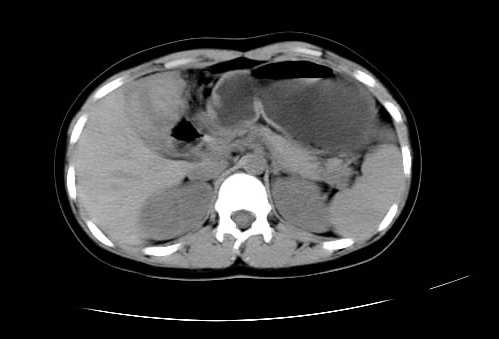

女 16岁  右上腹痛一天,无其他不适

肿块最大径位于十二指肠降段与水平段移行处,并且与肝脏压迹呈“0”形征,可以考虑位于肝外并与胃肠道关系紧密,考虑胃肠道间质瘤(gist)可能较大,须除外神经节起源肿瘤。

肿块与十二指肠关系密切,支持间质瘤诊断.肝脏与结肠均为受压改变.

右下腹巨大肿快,密度不均匀,内见坏死低密度区,边界清楚,与周边胀器明显有分界,未见强化,多考虑来源于间叶组织的良性肿物.

我坚决反对您的观点,该病例定位:横结肠肝曲与升结肠之间的肠系膜及部分肠壁。请看下图:

病灶巨大,少部分向肠腔内生长,大部分向长腔外生长。其密度不均匀,增强显示明显不均匀强化,并见有大片状始终不强化的不规则坏死液化区。虽然病灶中上部形态尚可,病人又如此年轻,但中下部形态、密度、强化特点强烈提示为恶性病灶。综上,我考虑本病例为:恶性胃肠道间质瘤。